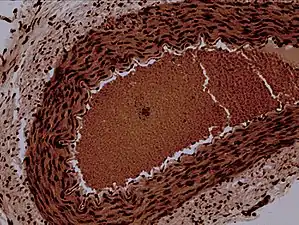

Rabbit arteriole at 100X

An arteriole is a small-diameter blood vessel in the microcirculation that extends and branches out from an artery and leads to capillaries.[1]

Arterioles have muscular walls (usually only one to two layers of smooth muscle cells) and are the primary site of vascular resistance. The greatest change in blood pressure and velocity of blood flow occurs at the transition of arterioles to capillaries. This function is extremely important because it prevents the thin, one-layer capillaries from exploding upon pressure. The arterioles achieve this decrease in pressure, as they are the site with the highest resistance (a large contributor to total peripheral resistance) which translates to a large decrease in the pressure.[2]